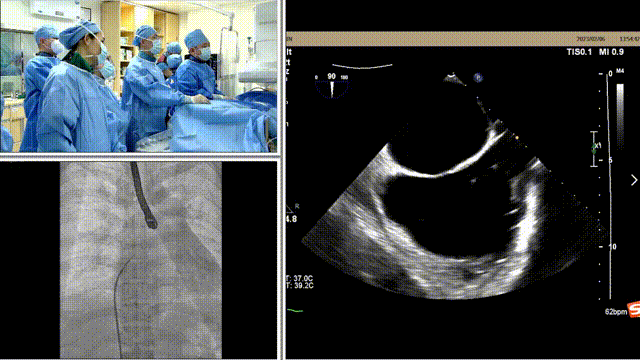

经导管二尖瓣置换术治疗功能性二尖瓣反流一例

经典病例周周谈丨珠海市人民医院姜小飞主任团队完成一